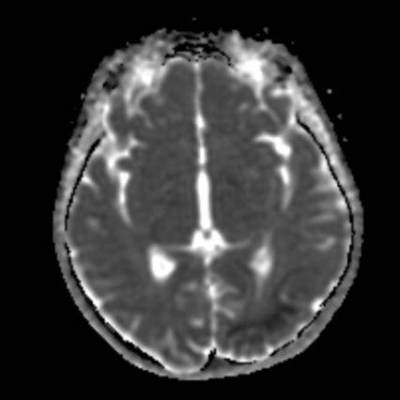

- A) Aksiyel FLAIR görüntülerde parietooksipital lobda kortikal hiperintensite (ok) ve difüzyon görüntülerde kısıtlanma alanları izleniyor (oklar). Ertesi gün çekilen kontrol MRG’de FLAIR serilerde yeni gelişen oksipital bölgede kortikal hiperintensite (ok) izlenmektedir.

- MRG’de akut fazda T2/FLAIR hiperintensiteyle birlikte giral şişme ile karakterize enfarkt-benzeri lezyonlar ve subkortikal beyaz cevher tutulumu görülür. DWI’da artmış sinyal dikkat çekmekle birlikte ADC değerlerinin normal ya da hafif artmış olması, baskın sürecin vazojenik ödem olduğunu gösterir.